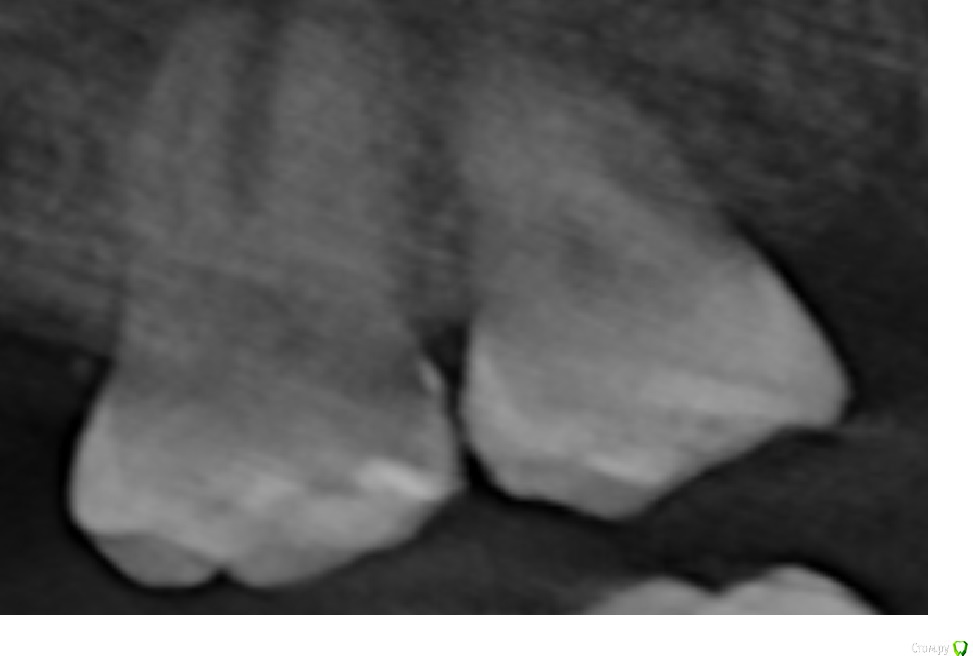

Vania777 Опубликовано 14 сентября, 2020 Поделиться Опубликовано 14 сентября, 2020 (изменено) так как есть кариозная полость ( опираясь на данные снимка) с правого бока, возможно придется вскрывать каналы и возможно удалять нерв ( от 7 до 20 тыс цена вопроса ) , с виду зуб абсолютно здоровый и не болит, просто хочу установить имплант на соседнее место взамен удаленного зуба и сказали обязательно лечить соседний зуб (тот что слева на фото) , действительно ли такой объем работы нужно делать, с удалением нерва ? Изменено 14 сентября, 2020 пользователем Vania777 Ссылка на комментарий

red_butler Опубликовано 15 сентября, 2020 Поделиться Опубликовано 15 сентября, 2020 снимок не информативен то что Вы показываете, является панорамной реконструкцией компьютерной томограммы, этот снимок не информативен. Нужны или срезы Кт зоны интереса, или вся Кт (но ее не все доктора смогут или захотят скачать) Ссылка на комментарий

Vania777 Опубликовано 15 сентября, 2020 Автор Поделиться Опубликовано 15 сентября, 2020 то что Вы показываете, является панорамной реконструкцией компьютерной томограммы, этот снимок не информативен. Нужны или срезы Кт зоны интереса, или вся Кт (но ее не все доктора смогут или захотят скачать)Это мне записали на болванку , еще там есть трехмерная реконструкция челюсти и зубов , я так понимаю что сама томограмма в оригинале весит гигабайты и на диск видимо не влезет Ссылка на комментарий